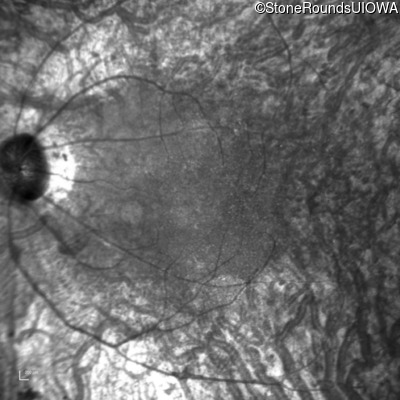

Infrared Fundus Photograph - Left - 20/80 -2

Exemplar